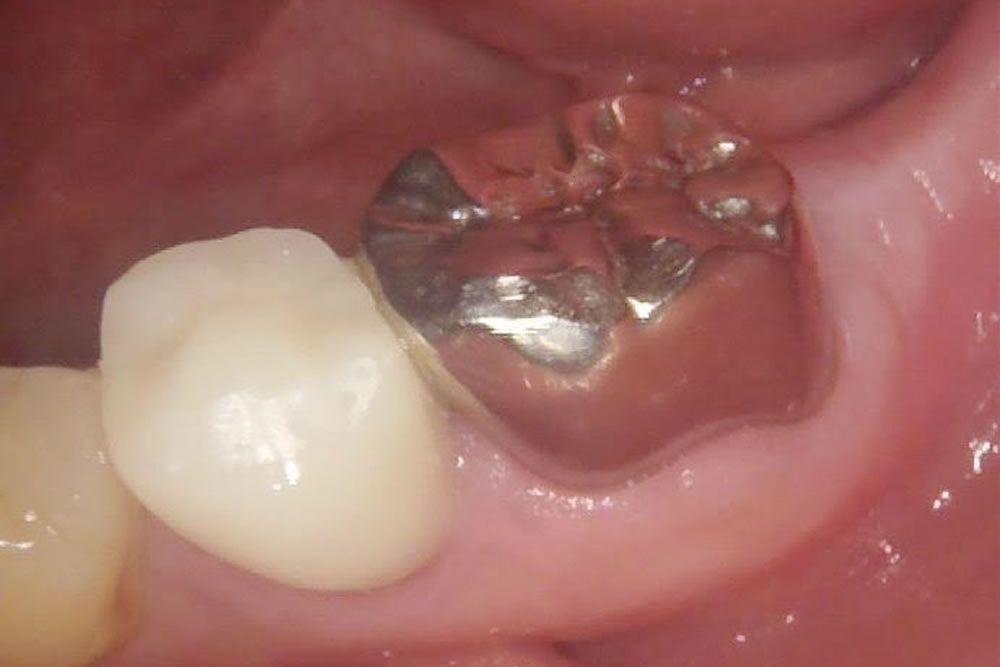

段差が気になる銀歯をセラミックで改善した症例

年齢

40代

性別

男性

症例を見る